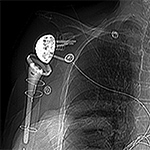

Periprosthetic 3D Reconstruction. (A) 3D reconstruction of osseous anatomy surrounding right total shoulder arthroplasty without dual-energy technique demonstrates significant artifact limiting evaluation of hardware and glenohumeral joint. (B) Dual-energy CT 3D reconstruction focused on metallic hardware demonstrates excellent visualization of hardware with metaglene screw fracture (arrow). Dual Energy CT. (A) Axial CT image acquired with dual energy technique demonstrates minimal artifact secondary to sacroiliac joint screws. (B) Coronal multi-planar reformation demonstrates excellent visualization of the osseous anatomy and hardware with further minimization of artifact.